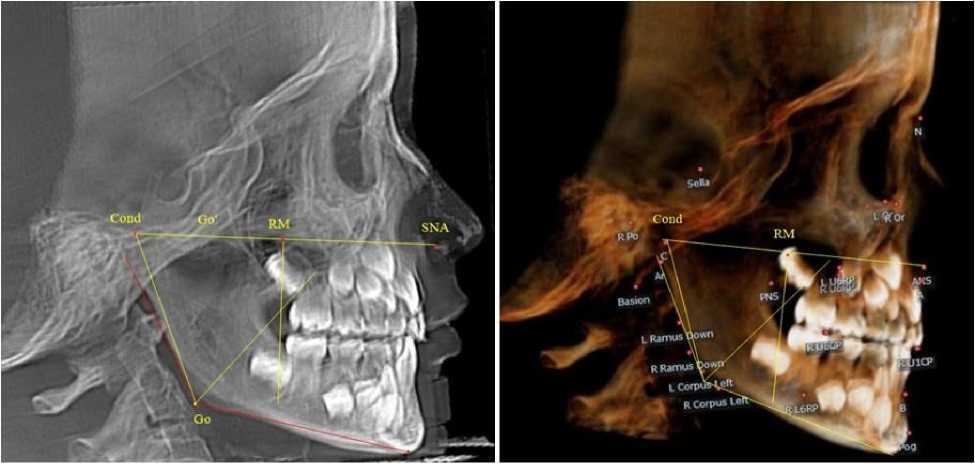

При анализе боковых телерентгенограмм и трехмерной модели установлено, что положе- ние зубов и челюстей относительно реперных линий было близким по значениям, полученным при анализе ортопантомограмм. Биссектриса угла Cond-Go-Ме, так же, как и на ортопантомограмме, располагались позади от формирующихся зачатков вторых постоянных моляров нижней челюсти (рис. 8).

После полного замещения молочных зубов постоянными продолжалась минерализация и формирование корней постоянных премоляров, клыков и вторых моляров. Зачатки формирующихся вторых верхних постоянных моляров, так же, как и у детей предыдущей группы, располагались впереди ретро молярной вертикали (рис. 9).

Рис. 7. Ортопантомограмма ребенка 8 лет после прорезывания постоянных резцов

а                                                   б

Рис. 8. Особенности боковой телерентгенограммы (а) и 3D-модели (б) ребенка 8 лет после прорезывания постоянных резцов

Рис. 9. Рентгенограмма ребенка 12 лет после замещения молочных зубов постоянными

Биссектриса угла Cond-Go-Ме располагались позади от формирующихся зачатков вторых постоянных моляров нижней челюсти. После прорезывания вторых постоянных моляров происходило полное формирование постоянного прикуса. В этот период особенности рентгенологической анатомии, как правило, определялись наличием или отсутствием зубов мудрости (или их зачатков) в челюстных костях.